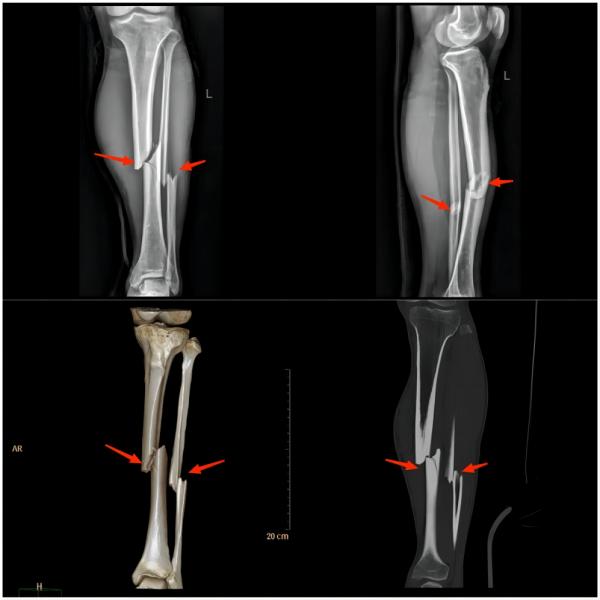

④ 小腿损伤

运动损伤知识科普宣传内容,关于足球运动损伤调查问卷

(上图为左胫腓骨双骨折)

常见原因:比赛的时候由于紧张地争抢、快速地跑动与铲球,常常被对手的球鞋、膝关节以及小腿踢撞,引起小腿肌肉挫伤、皮下血肿、肌肉断裂以及骨的损伤(如胫腓骨骨折)等。